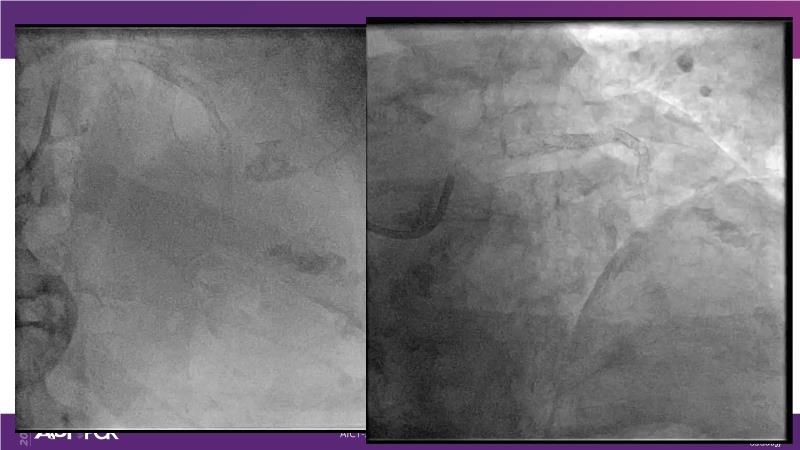

Cracking calcium: best practices to integrate intravascular lithotripsy into your calcium management algorithm

With this session, keep up to date on the evidence, trials and outcome data for intravascular lithotripsy in severely calcified lesions. Learn how to use this technique in real-world patients and understand its role in the treatment algorithm for severely calcified coronary lesions.